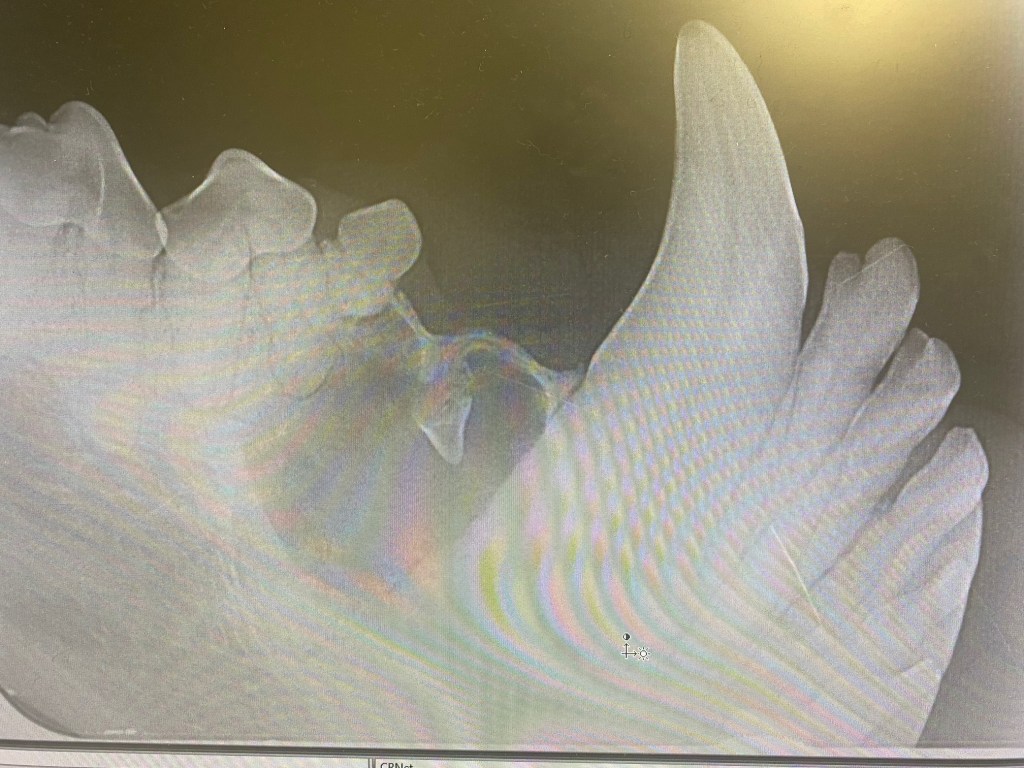

In this case a dentigerous cyst has formed around an unerupted supernumerary tooth (an extra 405) in a 7 year old dog. This has caused bone loss around the root of 405, the mesial root of 406 and also a significant amount around the distal surface of 404. All these teeth were therefore extracted. The lining of the cyst was removed by careful dissection, curettage of the socket wall, then flushing with saline. The site was sutured closed with simple interrupted 4/0 monoq.

The circular cysts can be seen over the root of 404

A cyst has formed around the unerupted crown of the supernumerary 405

There is a large amount of bone loss over the root of 404 which had to be extracted